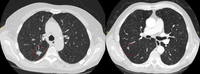

Computed tomography (CT) showing two left lower lobe peripheral nodules (one slightly spiculated and the other with smoother margins) in a patient presenting with fever, high inflammatory serum markers, and blood cultures confirming Streptococcus intermedius. Both nodules completely resolved following a course of linezolid, consistent with septic emboli

From the collection of Dr George Tsaknis, MD, PhD, FRCP(London), MRQA, MAcadMEd, PGCert; used with permission